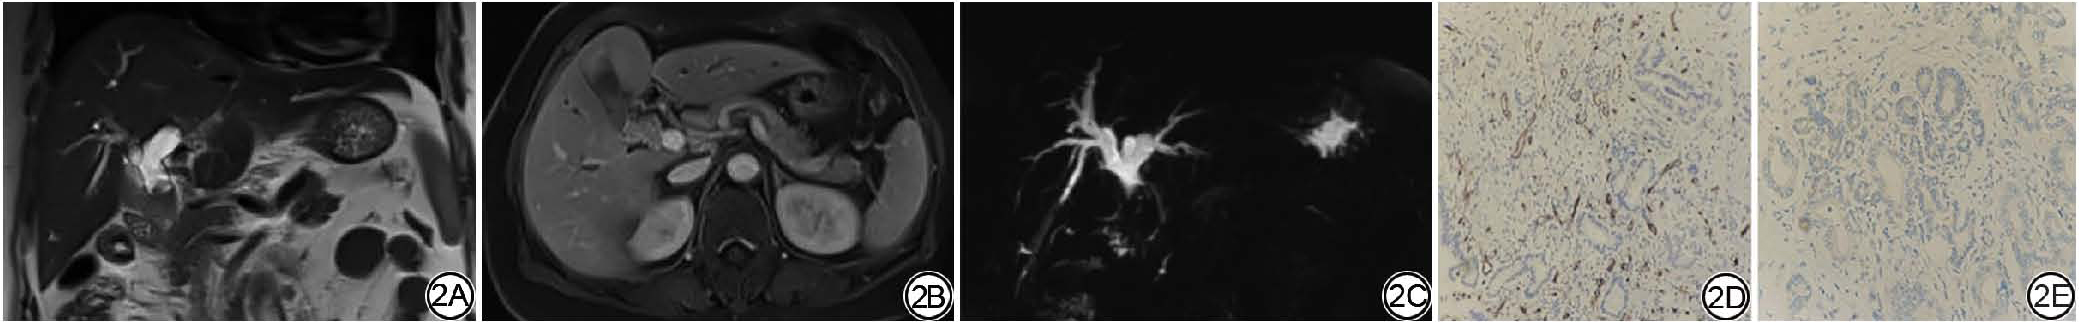

不同分化级别的ECCA患者的性别、年龄进行组间比较,差异无统计学意义(P>0.05),详见表2。高倍视野下VEGF无表达21例,低表达15例,中表达14例,未检测到高表达病例。50例ECCA患者标本组织的MVD为53(50,63),在各分化组MVD的差异具有统计学意义(P<0.05)。病理及影像图见图2

图2  男,45岁,肝外胆管癌,中分化。2A:冠状位T2WI;2B:轴位T1WI增强图像病灶强化较明显;2C:MRCP示胆总管内充盈缺损伴此水平以上肝内外胆管明显扩张;2D:微血管较丰富;2E:VEGF呈低表达。MRCP:磁共振胰胆管成像;VEGF:血管内皮生长因子。

Fig. 2  Male, 45 years old, extrahepatic cholangiocarcinoma, moderately differentiated. 2A: Coronal T2WI; 2B: The lesion enhancement in the axial T1WI enhanced image is relatively obvious; 2C: MRCP shows filling defect in the common bile duct accompanied by significant dilation of the intrahepatic and extrahepatic bile ducts above this level; 2D: The microvessels are relatively abundant; 2E: VEGF is expressed at a low level. MRCP: magnetic resonance cholangiopancreatography; VEGF: vascular endothelial growth factor.